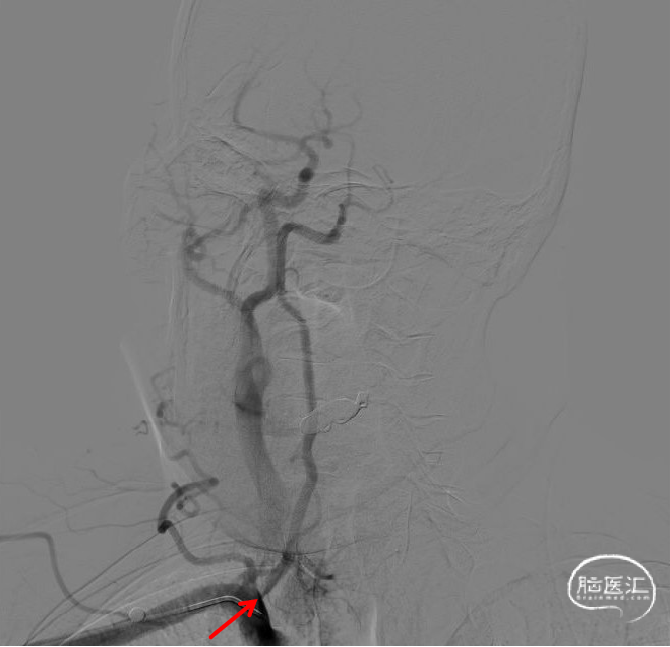

造影示支架完全覆盖狭窄段,与血管壁贴合良好。复查脑血管造影颅内远端血流通畅。

术后影像

术前影像

此患者主因“发作性头晕”入院。头颈部CTA提示右侧椎动脉起始段成中-重度狭窄,完善DSA证实右侧椎动脉V1段重度狭窄,且右侧椎动脉为优势椎,有明确的手术指征。

药物涂层支架在椎动脉狭窄治疗中具有显著优势。通过精确的定位和扩张,可以有效改善椎动脉狭窄,改善血流,从而缓解患者症状,另外可以有效预防支架内再狭窄。同时,我们也需要关注术后并发症的预防和处理,确保患者的安全和治疗效果,期待远期随访结果。